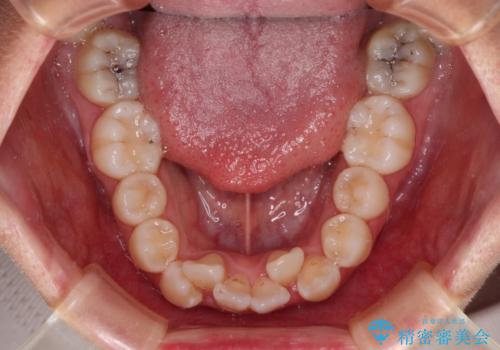

- 飛び出した上顎の前歯と八重歯を気にして来院された患者様です。

口元を積極的に引っ込めるために、上下左右の小臼歯計4本を抜歯することとしました。

舌の突出癖が強いため、しっかりと口元を引っ込めるため、舌のトレーニングをしっかりと行いながら矯正治療を行うこととしました。